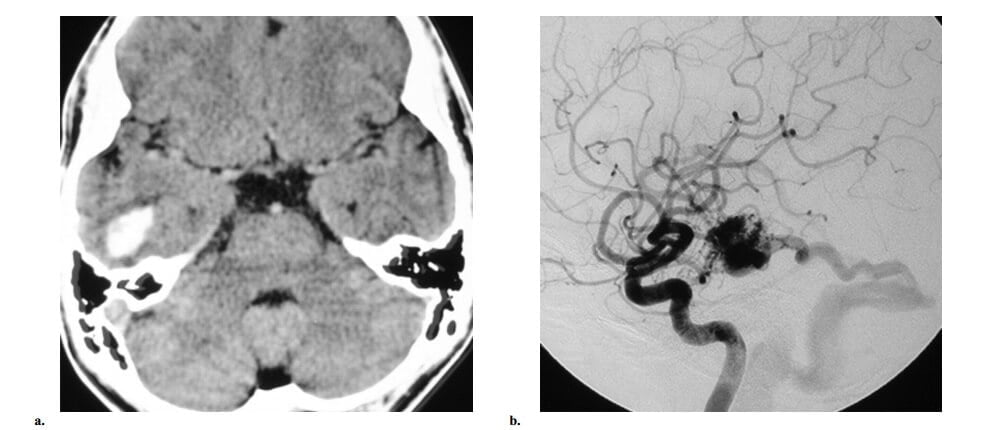

Bệnh moyamoya (tiếng nhật nghĩa là “khói thuốc lá”) là một bệnh lý tắc nghẽn ít gắp có nguồn gốc không rõ, về mặt kinh điển liên quan với các động mạch cảnh trong trên mấu giường yên, hố sau tương đối bình thường ở giai đoạn sớm. Thuật ngữ hội chứng moyamoya được dùng trong các trường hợp không thể xác định được nguyên nhân gốc (xơ vữa độngmạch, hội chứng Down, bệnh đa u sợi thần kinh, bệnh hồng cầu hình liềm hoặc một số bệnh khác). Thường có sự phát sinh rất nhiều mạch máu bàng hệ ở các nhánh xuyên vùng nền (các mạch máu moyamoya), đã được mô tả là hình ảnh khói thuốc lá trên hìnhchụp mạch máu não và các mạch máu bàng hệ xuyên màng cứng. Biểu hiện lâm sàng khác nhau giữa hai nhóm trẻ em và người lớn: hầu hết trẻ em có cơn thiếu máu thoáng qua hoặc nhồi máu não trong khi có một nửa số người lớn có xuất huyết nội sọ do vỡ các mạch máu bàng hệ moyamoya.

Manh mối hình ảnh học trên CT và MRI gồm sự hiện diện của nhiều tín hiệu flow voids thường thấy xuất phát từ bể nền và lan vào hạch nền hoặc đồi thị. Không có nidus thực sự nằm trong nhu mô não và không có dãn mạch máu (hình 11). Mặc dầu chẩn đoán có thể gợi ý bằng sự hiện diện của hẹp động mạch cảnh trong trên mấu giường yên hai bên trên hình chụp mạch CT và MR, nhưng chụp mạch máu vẫn còn cần thiết để đánh giá trước phẫu thuật cho việc tái tạo mạch máu của bệnh moyamoya. Tập hợp các đường bàng hệ thứ phát (các mạch máu bàng hệ moyamoya nhánh xuyên hạch nền, cấp máu xuyên màng cứng từ động mạch màng não giữa đến lối não và thông qua động mạch mắt đến các nhánh động mạch não trước) thường có thể được đánh giá chỉ bằng chụp DSA do kích thước nhỏ. Các nghiên cứu mới đây đã chứng minh rằng hình ảnh MR tưới máu và các khảo sát bảo tồn mạch máu não có thể chọn lựa trước phẫu thuật và theo dõi sau phẫu thuật sau khi phẫu thuật tái tạo mạch máu.

Hình 11: Bệnh moyamoya ở nữ 28 tuổi trải qua hai đợt xuất huyết nội sọ tái phát. (a) Axial CT cho thấy xuất huyết trong não thất. (b) Axial T2W thấy rất nhiều flow voids trong bể quanh gian não và quanh não giữa. Không thấy nidus. (c) Hình chụp động mạch cảnh trong thế trước sau thấy tắc động mạch cảnh trong trên mấu giường yên (mũi tên đặc) với rất nhiều mạch máu bàng hệ nhánh xuyên (đầu mũi tên). Cùng ghi nhận có cấp máu bàng hệ xuyên màng cứng từ động mạch màng não giữa (mũi tên hở). (d). Chụp động mạch cột sống trước sau cho thấy có liên quan các động mạch não sau, cùng với việc không có mạch máu bàng hệ hình khói thuốc lá gợi ý bệnh ở giai đoạn sau.